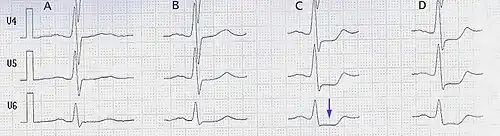

Belastungs-EKG

A in Ruhe

B bei 75 Watt

C bei 100 Watt

D bei 125 Watt

Das Belastungs-EKG wird meist mit einem Fahrradergometer aufgezeichnet, abhängig vom Zustand des Patienten entweder im Liegen oder Sitzen. Es stellt den nächsten Schritt in der Diagnostik bei Verdacht auf eine koronare Herzerkrankung dar. Die Sensitivität (50–70 %) und Spezifität (60–90 %) sind bedeutend höher als beim Ruhe-EKG. Wie hoch, ist u. a. abhängig vom Schweregrad der Erkrankung, vom Geschlecht und vom Ausmaß der Belastung (Erreichen der Ausbelastungs-Herzfrequenz). Der Verdacht auf eine bestehende chronische KHK wird durch Erregungsrückbildungsstörungen unter Belastung, das vermehrte Auftreten von Extraschlägen oder plötzlichen Blutdruckabfall unter Belastung erhärtet.

Manche Herzmedikamente (Digitalisglykoside) erschweren die Beurteilbarkeit von Erregungsrückbildungsstörungen, auch kann die Einnahmen von herzfrequenzsenkenden Medikamenten die Beurteilbarkeit einschränken, da die Zielfrequenz nicht erreicht wird und der Patient so nicht voll ausgelastet ist. Der Verdacht auf einen akuten Herzinfarkt ist eine absolute Kontraindikation, und auch bei schon vor der Untersuchung deutlich überhöhtem Blutdruck oder Herzfrequenz sollte sie nicht durchgeführt werden.